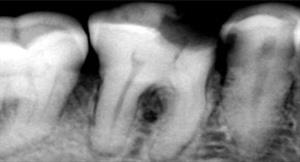

Before

A root canal procedure (endodontic treatment) is often required to save an infected tooth. Bacteria can enter a tooth through a cavity or a damaged filling. When this happens, the tooth can become abscessed, meaning the pulp inside the tooth becomes infected. An abscessed tooth can be quite painful and cause swelling in the surrounding gum tissues. If left untreated, it can cause several oral health problems. A root canal procedure removes the infected pulp and any other infected tissues within the tooth.